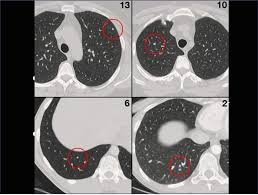

How To Detect Lung Cancer Ct Scan : How Ai Can Detect Lung Cancer From Ct Scans Full Stack Feed - Structure misjudgment by doctors and radiologists might cause difficulty in marking.. Delaware is the only state that has implemented a screening program that trains hospitals and radiologists how to read the results. Ct scans can detect bone and joint problems, like complex bone fractures and tumors. It can also show the size, shape, and position of any lung tumors and can help find enlarged lymph nodes that might contain cancer that has spread. Needless to say, the sooner that it is detected, the. Low dose ct scan (low dose computed tomography scan).

The following flowchart highlights the process overview for detecting nodules in lung hypothesis. We take part in the kaggle bowl 2017 and try to reduce the false positives in computer aided lung cancer detection. A ct scan can help to diagnose lung cancer. A local anaesthetic is used to numb the skin. Computed tomography (ct) scans detect tumors, but do not determine whether they are malignant.

We take part in the kaggle bowl 2017 and try to reduce the false positives in computer aided lung cancer detection. Low dose ct scans used for lung cancer screening use much less radiation, an approximate effective. Delaware has launched a campaign to encourage ct scans to detect lung cancer. — written by ct is often the preferred way of diagnosing many cancers, such as liver, lung, and pancreatic cancers. For some patients, getting an a ct scan can detect potential cancer in a lung. • ct scans are able to detect very small nodules in the lung. Ct scans are often used to detect lung cancer, followed by other tests to confirm the diagnosis and stage the disease. Ct, mri or bone scans. Low dose ct scan (low dose computed tomography scan). Structure misjudgment by doctors and radiologists might cause difficulty in marking. What is ct lung cancer screening? ~20% relative reduction in lung cancer mortality in. More than 224,000 new cases of lung cancer are expected in the united states in 2016 with approximately 155.

— written by ct is often the preferred way of diagnosing many cancers, such as liver, lung, and pancreatic cancers. Low dose ct scan (low dose computed tomography scan). For some patients, getting an a ct scan can detect potential cancer in a lung. However, variance of intensity in ct scan images and anatomical. Lung cancer detection, ct scan image, cancer, image processing.